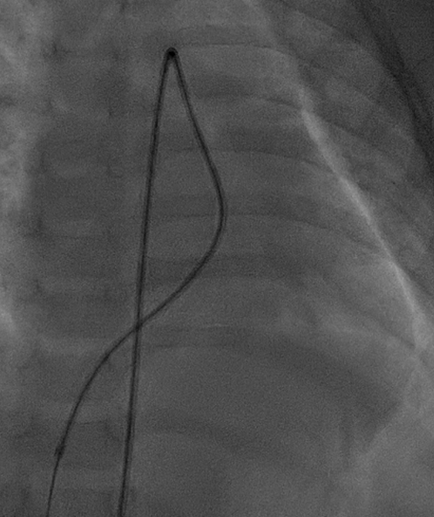

通过5F左冠造影管将0.032 in超滑导丝260 cm通过瘘口,进入下腔静脉后,使用网篮抓捕导丝建立轨道。

图片